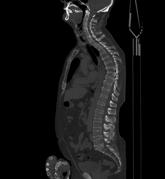

Bei dieser Untersuchung ist keine spezielle Vorbereitung notwendig. Meist werden Sie Kontrastmittel intravenös verabreicht bekommen. Bei der Darstellung der Speiseröhre müssen Sie vor der Untersuchung auf dem Untersuchungstisch einen Becher Kontrastmittel trinken.

Die Untersuchungsdauer beträgt ca. 10 Minuten.

Je nach Fragestellung müssen Sie vor der Untersuchung Kontrastmittel trinken, damit der Magen- Darm- Bereich besser dargestellt werden kann. Die Kontrastmittelmenge beträgt meist 1 Liter, den Sie über einen Zeitraum von etwa 1 Stunde trinken müssen. Bei manchen Untersuchungen ist die Gabe von Kontrastmittel über eine Vene (zusätzlich) erforderlich. Manche Erkrankungen erfordern auch eine Kontrastmittelgabe über den Enddarm, hierfür müssen Sie zu Hause keine besonderen Vorbereitungen treffen. Dabei wird Ihnen über ein Darmrohr ein Liter verdünntes jodhaltiges, vorgewärmtes Kontrastmittel verabreicht, nachdem der Arzt den Enddarm untersucht hat.

Die Untersuchungsdauer beträgt zwischen 20 Minuten bis 90 Minuten bei oraler Kontrastmittelgabe.

Bei Untersuchungen vom Becken sind keine speziellen Vorbereitungen notwendig. Nur selten wird auch eine intravenöse Kontrastmittelgabe erfolgen. Manche Erkrankungen erfordern eine Kontrastmittelgabe über den Enddarm, hierfür müssen Sie zu Hause aber keine besonderen Vorbereitungen treffen. Dabei wird Ihnen über ein Darmrohr ein Liter verdünntes jodhaltiges vorgewärmtes Kontrastmittel verabreicht, nachdem der Arzt den Enddarm untersucht hat.

Die Untersuchungszeit beträgt ca. 10-20 Minuten.